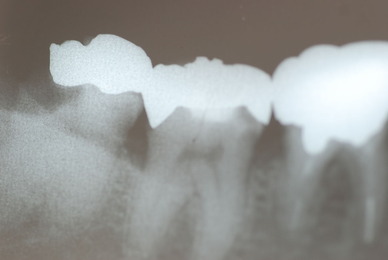

入れ歯の話から入りました。色々不満で注文があるようです。でも話が一段落して口腔内を調べると殆どの歯が重症で抜けそうな歯だらけなのです。

なぜ病気になるのかわからない方が多すぎます。歯が抜けるのは病気だからです。病気を治さずに何かお口の中に入れても土台である歯が抜けてしまっては同じことなのです。

何故歯が悪くなるのか、歯周病で抜けるのか分からなければ何を入れても歯は悪くなり抜けていくのです。

病気を治しましょう。それから差し歯や入れ歯を入れましょう!物を入れれば入れるほど、磨き方や掃除の仕方が上手にならなければ、すぐ抜けてくるのです。